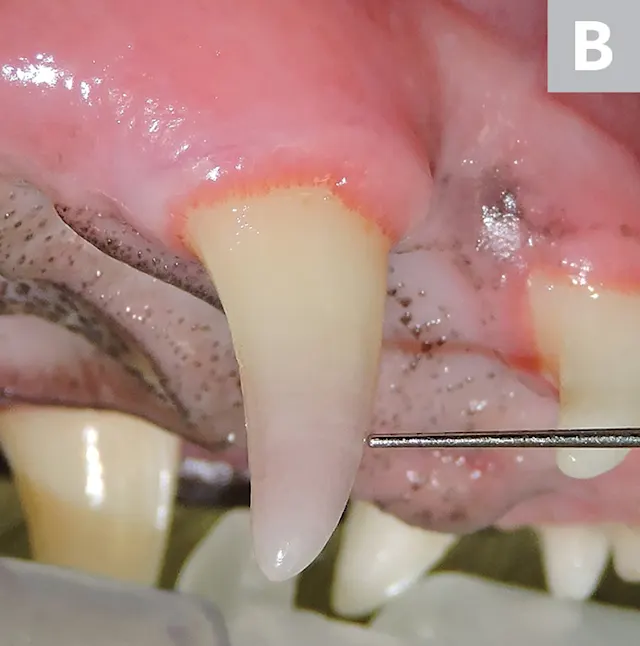

Figure 2

Uncomplicated chip fracture of the right mandibular canine tooth. The tooth has been traumatized and should be monitored for signs of pulpitis. A dental explorer would not be able to enter the pulp chamber for this type of fracture.